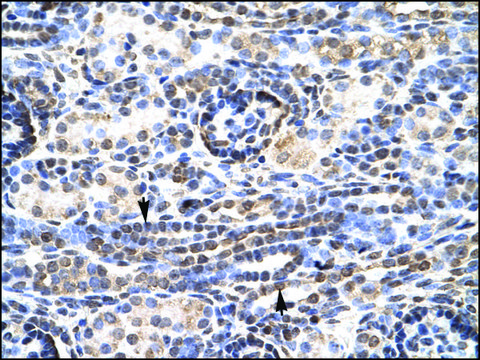

Anti-KLF9 antibody produced in rabbit affinity isolated antibody